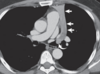

Atelectasia compresiva o de relajación en derrame pleural maligno secundario a adenocarcinoma metastásico. Una tomografía computarizada con contraste muestra un gran derrame pleural izquierdo con desplazamiento hacia la derecha del mediastino y atelectasia compresiva completa del lóbulo inferior izquierdo (flechas).